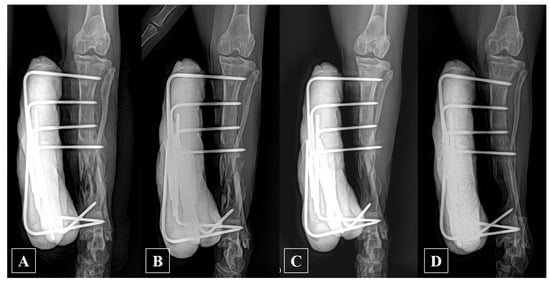

2.2. Anesthesia and Surgical Treatment

2.3. Postoperative Management and Prognosis